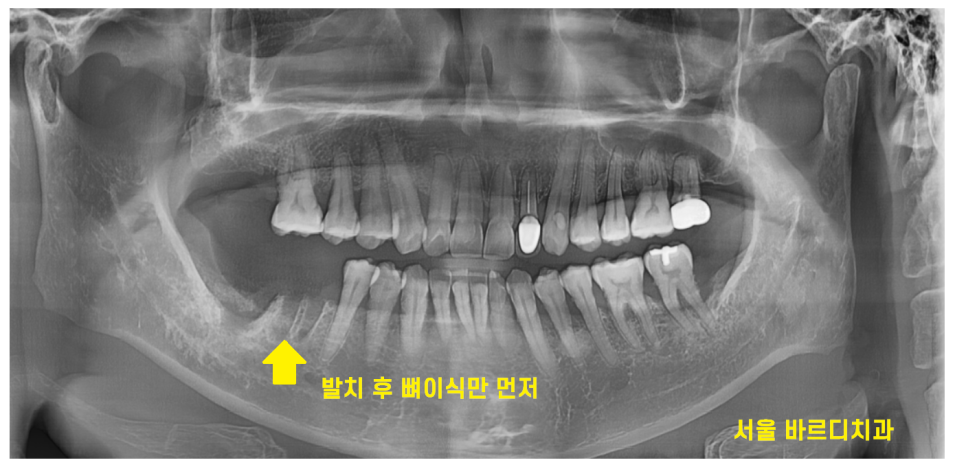

23.08.31

일반적으로는 임플란트와 뼈이식을 동시에 진행하지만..

뼈가 거의 없는 경우 1차적으로 뼈만 이식 후

뼈가 충분히 만들어지면

추후 임플란트 수술을 진행합니다.

이렇게 되면 치료 기간이 길어진다는 단점이 있죠.

이를 뽑는 발치 후 뼈이식을 같이 진행하였습니다.